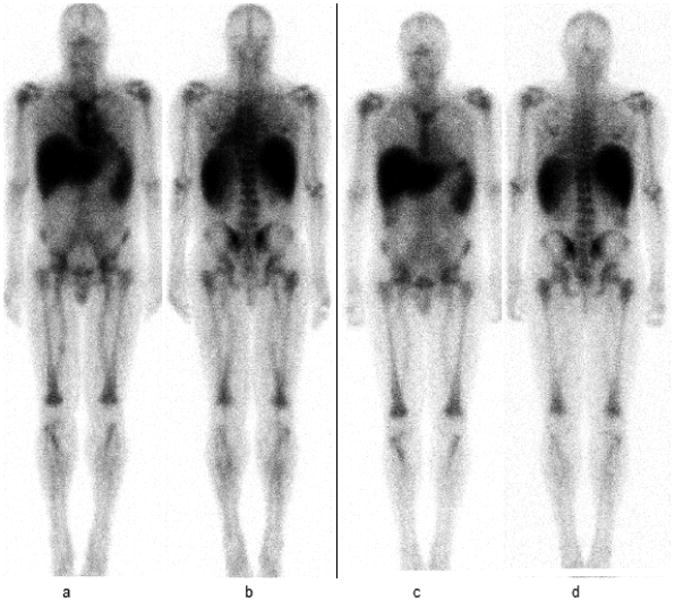

Thirty eight patients (from a total of 40 who completed the therapy on the research protocol) were included in this biodistribution analysis, as detailed in the patient eligibility section. An additional one patient from the five who initially consented but did not complete the therapy was excluded due to altered 111In- ibritumomab tiuxetan biodistribution (on 48 hours images there was intense tracer uptake in the liver and only faint visualization of the spleen) (Figure 2). Baseline characteristics of these 38 evaluable patients are summarized in Table 1.

Figure 2.

52 year old male with history of CD20 positive CLL/SLL which was excluded from the trial due to safety reasons concerning liver toxicity.

Whole body planar anterior image (a) and posterior image (b) obtained at 24 hours show intense radiotracer uptake in the liver and only faint uptake in the spleen and kidneys. At 48 hours images (c and d) there is uptake in the liver without significant uptake in other organs worrisome for progressive accumulation of radiotracer in the liver for the next several days, concerning for liver toxicity. Uptake values were 55% at 24 hours and 60% at 48 hours.